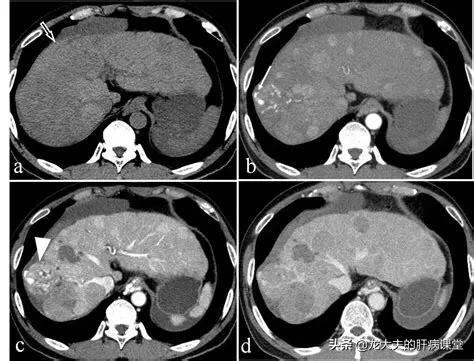

Cet homme d'âge moyen, ayant des antécédents d'hépatite B chronique, présentait à l'échographie une hypoéchogénicité irrégulière dans le segment inférieur du lobe droit du foie, ainsi qu'un taux élevé d'alpha-fœtoprotéine dans les tests de laboratoire. Un examen complémentaire par résonance magnétique a révélé une zone arrondie classique à faible signal, avec un rehaussement irrégulier au scanner de rehaussement, ce qui a permis de préciser qu'il s'agissait d'un petit carcinome hépatocellulaire, opéré depuis près de trois ans.

La tomodensitométrie améliorée peut également confirmer le diagnostic pour les lésions typiques. Certains petits cancers du foie sont délicats et d'apparence atypique et peuvent nécessiter une IRM améliorée avec des agents de contraste spéciaux, ce qui est un peu plus coûteux et nécessite un rendez-vous préalable.